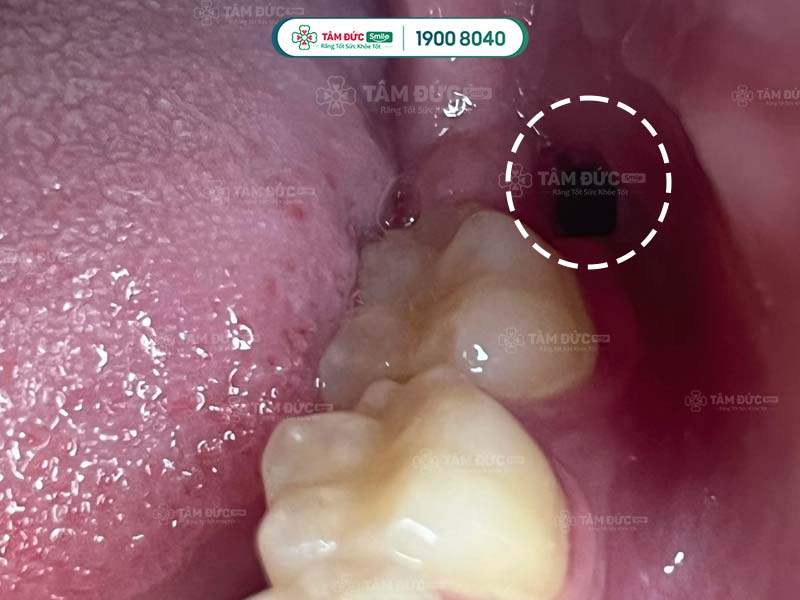

- Khô ổ răng.

1.4. Khô ổ răng nên nhổ răng khôn 2 tuần vẫn đau

Khô ổ răng còn được biết đến là tình trạng viêm xương ổ răng, thường xảy ra sau khi nhổ răng khôn. Xác suất bị khô ổ răng chỉ chiếm chưa tới 2% trong số các biến chứng sau khi nhổ răng thường. Với nhổ răng khôn, tỷ lệ xuất hiện của biến chứng này có thể lên tới 20%.

Nguyên nhân gây khô ổ răng là do Quý khách không vệ sinh, chăm sóc răng miệng đúng cách. Điều này đã tạo điều kiện để vi khuẩn, hóa chất xâm nhập vào bên trong gây khô ổ răng. Quý khách có thể gặp phải tình trạng đau nhức kéo dài, cơn đau lan tỏa ra xung quanh, kèm theo đó là chứng hôi miệng.